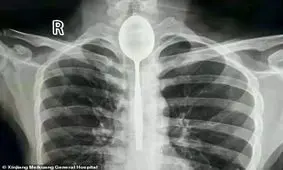

یک جوان چینی بعد از قورت دادن قاشق یک سال زندگی کرد او بعد از یک سال به پزشک مراجعه کرد.